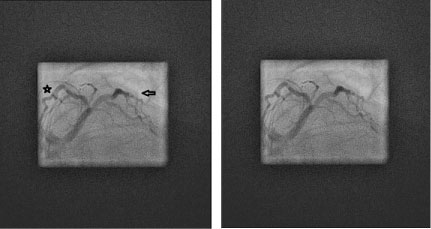

Figure 2: (Labeled and unlabeled).

An elongated left main coronary artery gives rise to the left anterior descending artery (star) which then gives off a substantial bifurcating diagonal branch (arrow) in the left anterior oblique, caudal ("spider") view via cinematography during the left heart catheterization. View Figure 2

Figure 3: (Labeled and unlabeled).

This is an 8x magnification of the left anterior oblique, caudal ("spider") view via cinematography during the left heart catheterization, showing the left anterior descending artery (star) and large diagonal branch (arrow) but there is also no sign of a left circumflex stump or cleft that may suggest an occluded left circumflex branch. View Figure 3